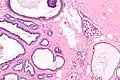

Micrograph of collagenous spherulosis with the characteristic histomorphology - intratubular eosinophilic material with a spoke-like arrangement. H&E stain.

Collagenous spherulosis is characterized by a tubular/cribriform architecture with intratubular eosinophilic material that classically is arranged like the spokes of a wheel ("radial spikes"). There is usually no mitotic activity, and two cells populations (epithelial & myoepithelial) are present, like in benign breast glands.

The lesions are typically small (less than 50 spherules per lesion, less than 100 micrometers in size) and may be multifocal.